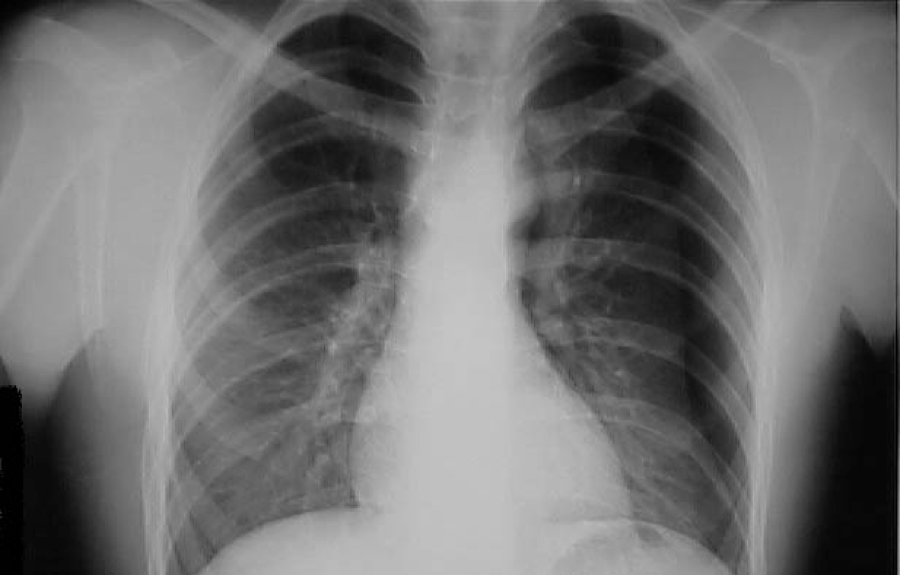

Injuries that immediately compromise ventilation and oxygenation should be identified during the initial assessment of the trauma patient and treated appropriately. Examples include pneumothorax and haemothorax. These patients are always admitted.

Some injuries result in severe respiratory compromise hours or even days after injury. Minor injuries can be a marker for more severe injuries. The Trauma Service has a liberal admission policy for patients with seemingly minimal chest trauma.

4. Pulmonary contusion